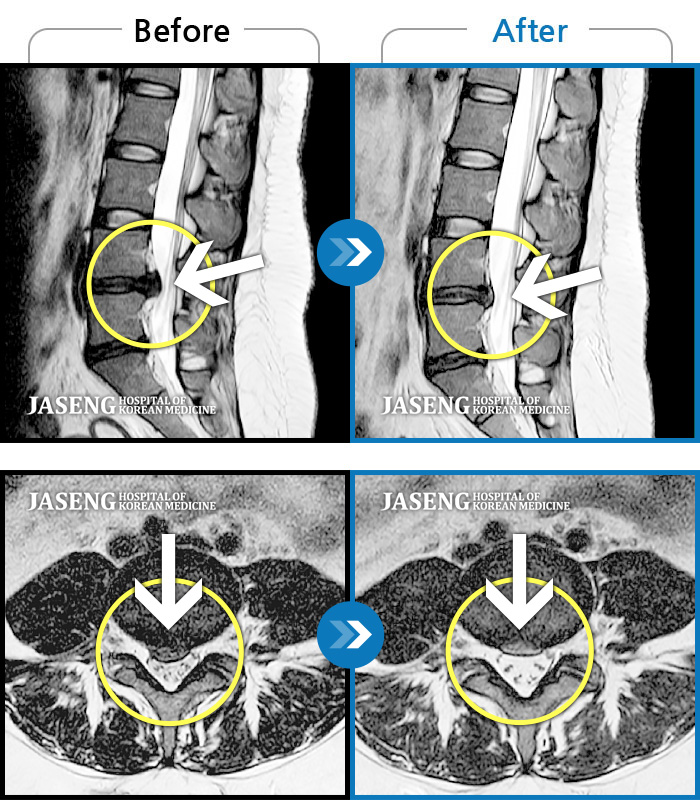

Before

After

허리 통증이 심해 어떤 자세도 힘들며, 우측 다리쪽으로 저리고 통증이 내려온다.

2021.10.26 ~ 2022.04.09